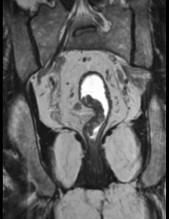

问题 男,70岁,下腹部腹胀、腹痛、排便困难,逐渐加重,MRI示直肠内不规则充盈缺损,请选择最佳诊断结果 ( )

选项 A.直肠息肉 B.直肠癌 C.直肠间质瘤 D.直肠转移瘤 E.直肠淋巴瘤

答案 B